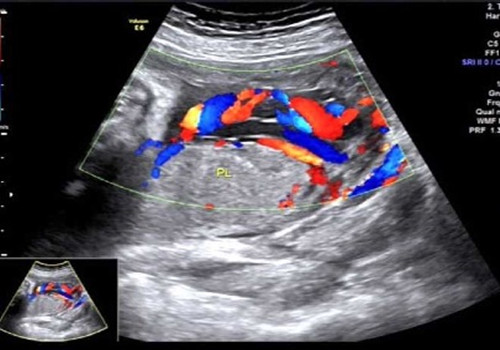

2017年7月10日上午就是在这间小黑屋里,一名34周孕妇正在进行产科常规超声检查,当探查到胎盘时,朱新娟医师一脸凝重,她发现了异常!经科主任吴建军、副主任医师赵莹会诊,发现该孕妇腹中胎儿脐带走形异常、并异常插入胎盘,沿胎膜走行约5.2cm后才进入胎盘实质,且血管聚集成堆于宫颈内口处,考虑脐带帆状插入胎盘并血管前置。此现象是非常少见的产科急症!极易造成血管断裂!大出血!造成胎儿死亡!而这一切,产妇和家属却全然不知。情况紧急,朱新娟立即电话报告产科危急值!

声像图示:脐带帆状插入胎盘并血管前置

产科接到危急值报告后,即刻将该孕妇收治入院,给予密切监护、治疗,并于7月20日上午9:40,为该孕妇行剖宫产,娩出一名2000g女婴,母女平安!数十分钟后胎盘娩出,确系少见的脐带帆状插入胎盘并血管前置!产科马主任激动地拉着吴主任的手说:“你们超声医生太棒啦!你们就是我们产科医生的眼睛!不但救了这对母女,也‘救’了我们产科医生啊!”